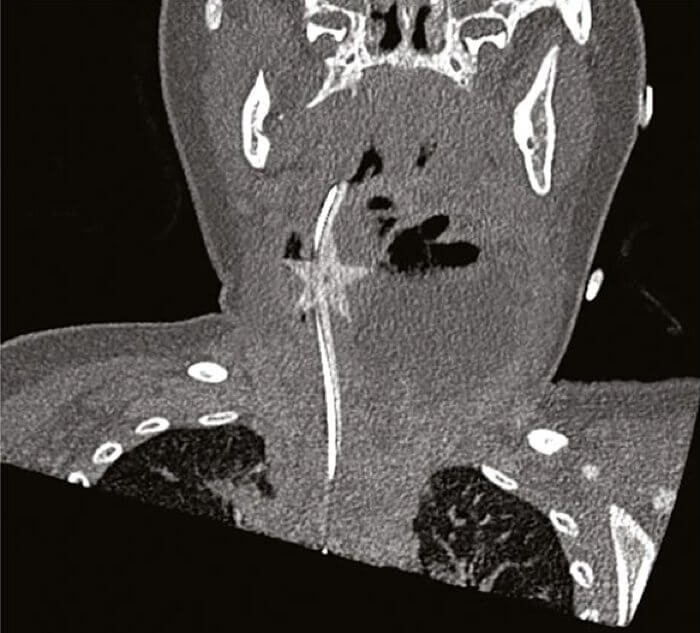

Частичка конфетти, обнаруженное в горле ребенка

На третьем приеме врачи наблюдали малую активность ребенка, замедление кровотока и другие тяжелые симптомы. Проведя еще один ряд исследований, работники больницы наконец-то выявили истинную причину болезненного состояния ребенка. Оказалось, что в горле ребенка застрял крошечный предмет в виде звезды, который на самом деле была частичка конфетти.

Врачи признали, что несмотря на гибкость, конфетти вполне могут застрять в верхних дыхательных путях, тем более у маленьких детей. Чтобы избавить ребенка от мучений, хирургам пришлось сделать разрез и вызволить звездочку. После этого ребенку давали антибиотики и со временем он пошел на поправку. Никаких инфекций и осложнений, к счастью ребенка и матери, не возникло. То есть история завершилась весьма хорошо.